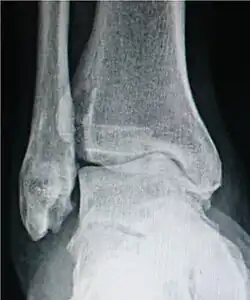

Ankle osteoarthritis.

For the ankle, the Kellgren–Lawrence scale, as described for the hip, has been recommended.[16] The distances between the bones in the ankle are normally as follows:[17]

Talus - medial malleolus: 1.70 ± 0.13 mm

Talus - tibial plafond: 2.04 ± 0.29 mm

Talus - lateral malleolus: 2.13 ± 0.20 mm